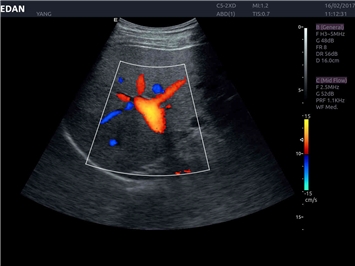

EDAN Acclarix LX4 представляет собой инновационную ультразвуковую систему, построенную на усовершенствованной платформе Acclarix. Сочетание высокого качества визуализации с интеллектуальным рабочим процессом делает эту систему оптимальным выбором для клиник, ценящих эффективность и экономичность.

• Тканевая допплеровская визуализация (TDI)

• Кардиологических исследований

• Сосудистой диагностики

Трехмерная реконструкция ЦДК:

Да

Цветовой допплер: